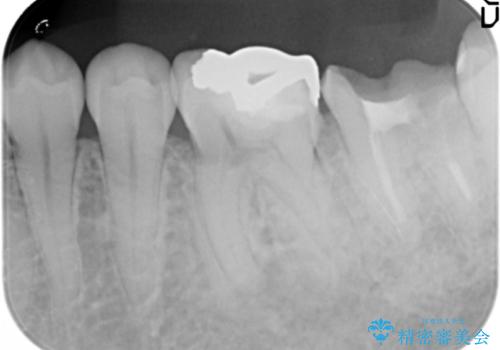

下の奥歯が虫歯になっており、痛みが生じていました。

左右の第二大臼歯は虫歯がひどく抜歯が必要な状態でした。

また、左下の第一大臼歯は歯が内側から吸収してしまう状態(外部吸収)が生じており、患者様と相談の上抜歯しました。